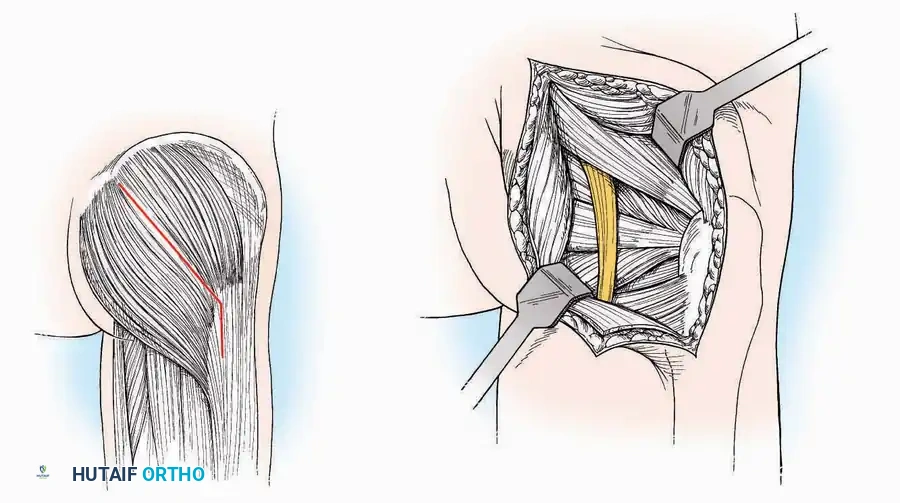

Lateral Approach (Extensile Lateral)

This is the workhorse approach for open reduction and internal fixation (ORIF) of displaced intra-articular calcaneal fractures.

Indications: ORIF of calcaneus fractures, lateral wall exostectomy, subtalar arthrodesis.

Positioning: Lateral decubitus with the operative leg up, or supine with a large bump under the ipsilateral hip to internally rotate the leg.

Surgical Technique:

* Incision: Begin the incision on the lateral margin of the Achilles tendon near its insertion. Extend it distally to a point 4 cm inferior and 2.5 cm anterior to the lateral malleolus. (For trauma, a classic L-shaped extensile incision is often used, dropping straight down anterior to the Achilles, then curving gently toward the base of the 5th metatarsal).

* Superficial Dissection: Divide the superficial and deep fasciae. It is imperative to create a "full-thickness" flap containing skin, subcutaneous fat, and periosteum to prevent flap necrosis.

* Nerve Protection: The sural nerve crosses the proximal and distal limbs of this approach. It must be identified and protected within the anterior flap.

* Deep Dissection: Isolate the peroneal tendons (longus and brevis). Incise and elevate the periosteum below the tendons to expose the lateral wall of the calcaneus.

* Tendon Management: If severe deformity or infection is present, the peroneal tendons may be divided via Z-plasty and repaired at the conclusion of the case, though this is rarely necessary in modern fracture care.